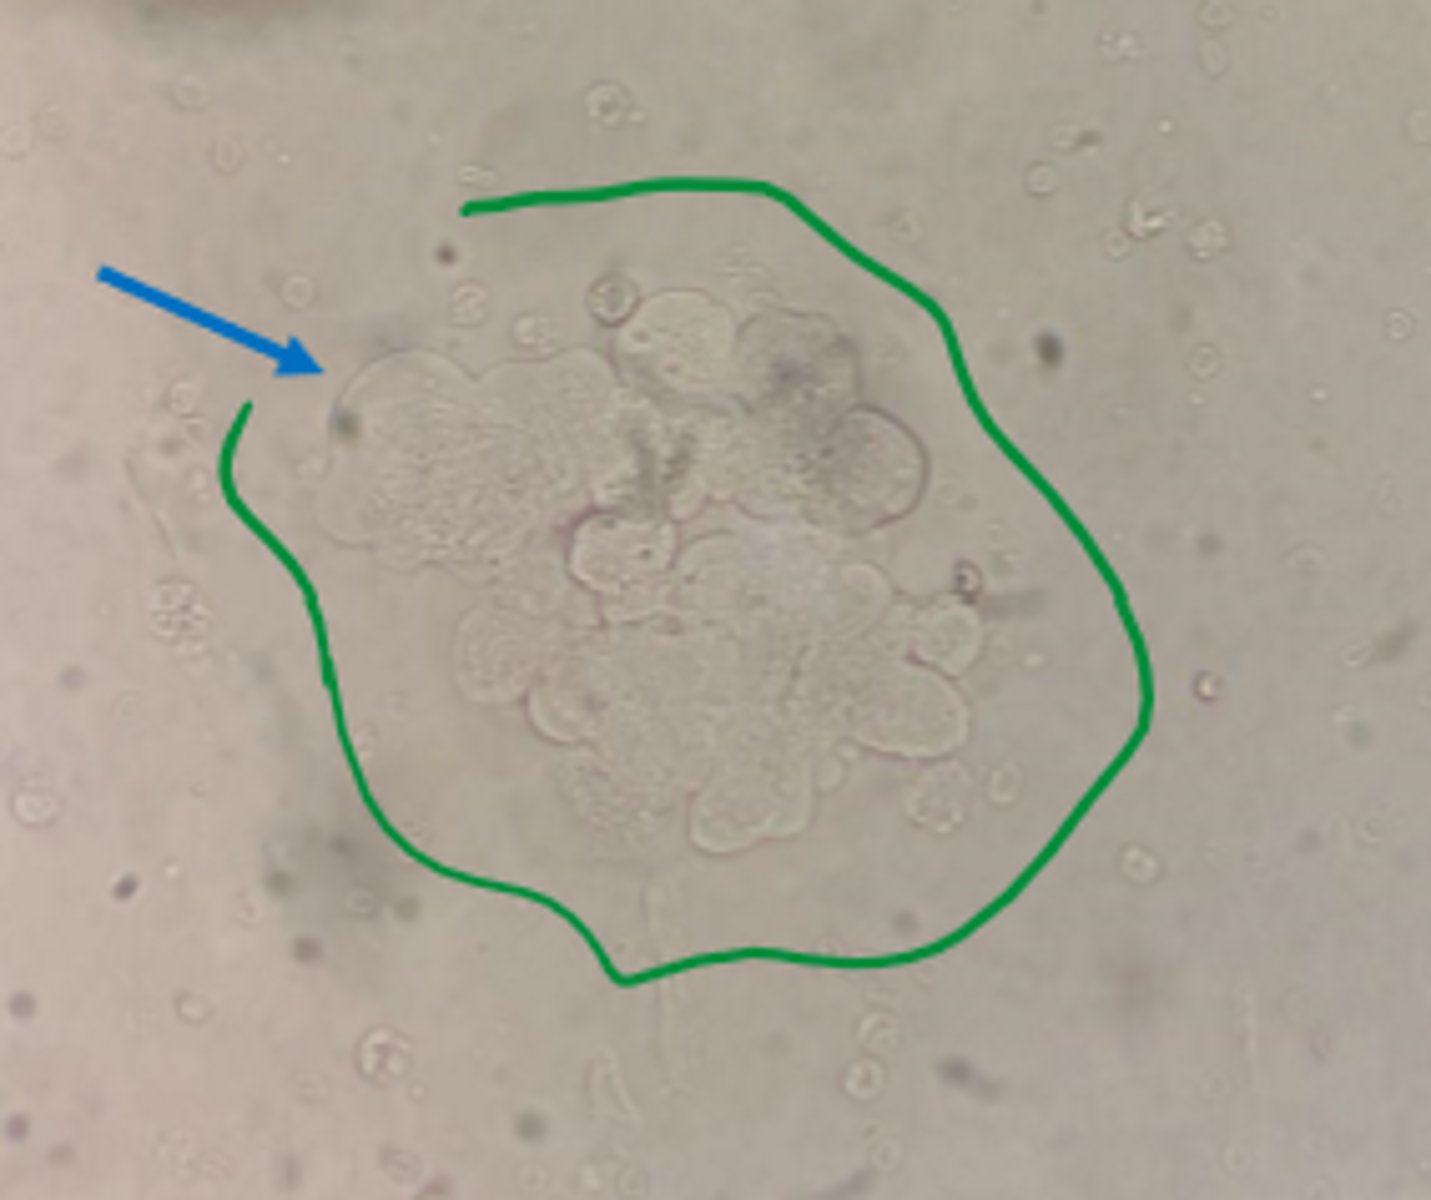

cellular cast

urine

RBC cellular cast

urine

WBC cellular cast

urine

epithelial cellular cast

urine